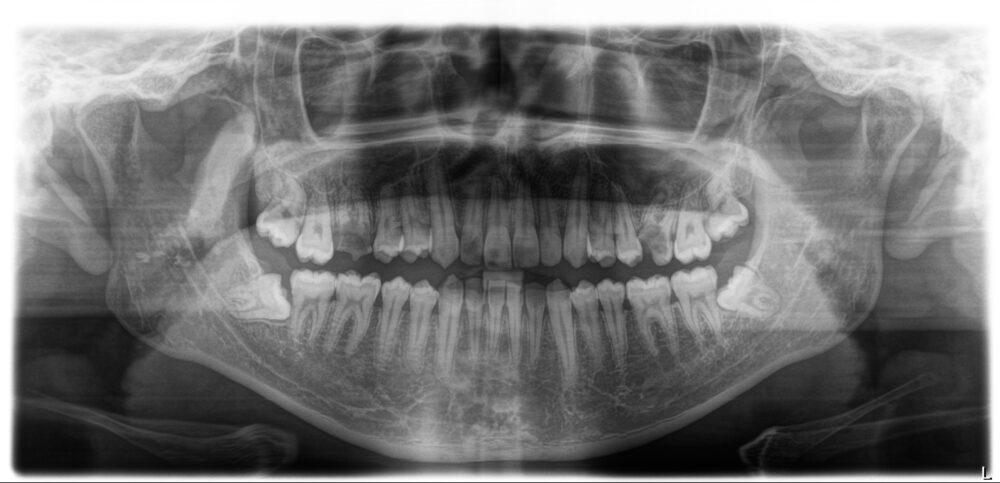

27才、男性です。

家族から「歯ぎしり」がひどいと指摘されたことが心配でお越しになりました。自分では10代後半に左下の奥歯(乳歯)が抜けてしまい、そのままにしていることで咬み合わせが悪くなったことが「歯ぎしり」の原因ではないか…と思っているとのことでした。

両側とも下の5番目の永久歯が生まれつきありません(先天的欠如歯)。

先天的に永久歯がないことや乳歯が残っていることで他の歯の位置がずれ、上下の顎の関係が狂ってしまいます。その結果、呼吸環境が悪化していことが「歯ぎしり」の一因になっている可能性があることを伝え、咬合診断の上、矯正治療とインプラント治療が必要であることをお話ししました。

初診より約2ヵ月後、右下の乳歯の抜歯を行い、アライナー治療を開始しました。

矯正治療開始より1年10ヵ月後、両側下の5番目にインプラントOpeを行い、3ヵ月後プロビジョナルレストレーション(暫間修復歯)を入れることになりました。